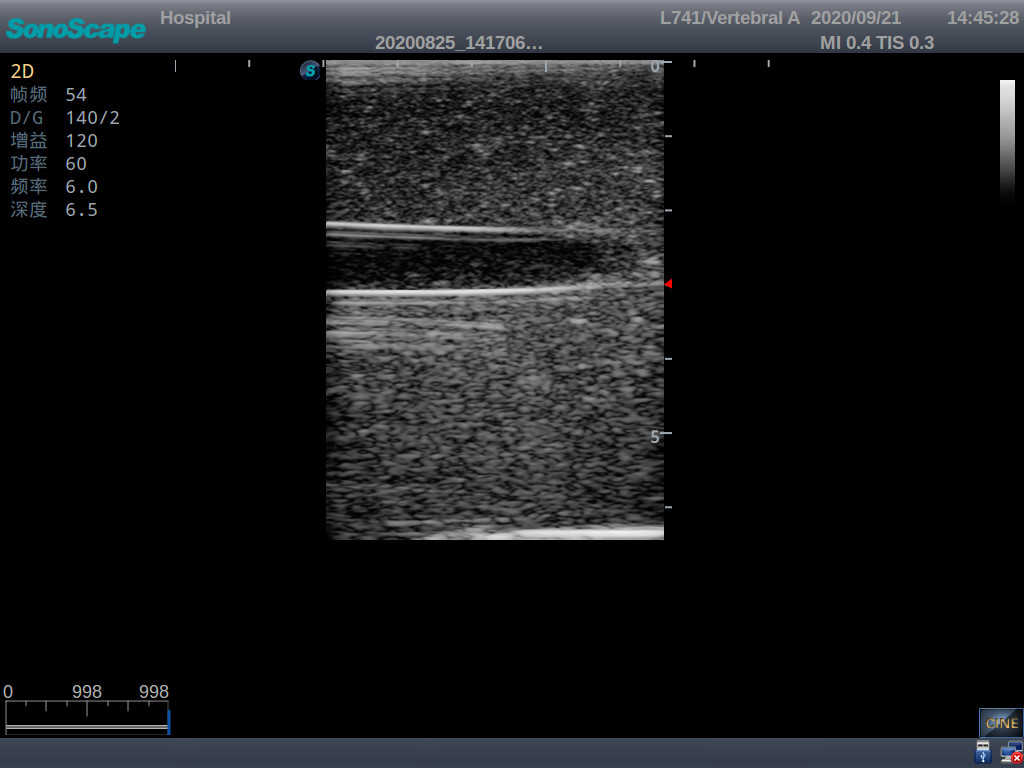

1) Made of high molecular polymer ultrasound material, close to real skin. It can conduct ultrasound-guided puncture exercises with various clinical models of real ultrasound machines

2) Clear and real images of arteries and veins

3) Showing physiological phenomena that veins are easier to be flatted than arteries under external pressure